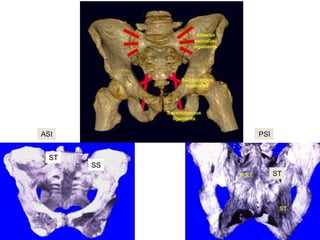

Anatomy of Pelvis : ligaments

 posterior ligaments are

stronger than anterior

ligaments:

 Posterior SI

 Anterior SI

 Interosseous ligaments

 Pubic symphysis

 Sacrotuberous

 Sacrospinous

 Sacrospinous resists

external rotation

 Sacrotuberous resists

rotational and vertical

shearing forces

ASI

ST

SS

PSI

Posterior Ligaments

 Ant. SI Joint – resist external rotation

 Post. SI and Interosseous – posterior stability by tension band

(strongest in body)

 Iliolumbar ligaments augments posterior complex

 Sacrotuberous (sacrum behind sacro-spinous into ischial

tuberosily vertically)Resists shear and flexion of SI joint

 Sacrospinous – (anterior sacral body to ischial spine

horizontally) resists external rotation